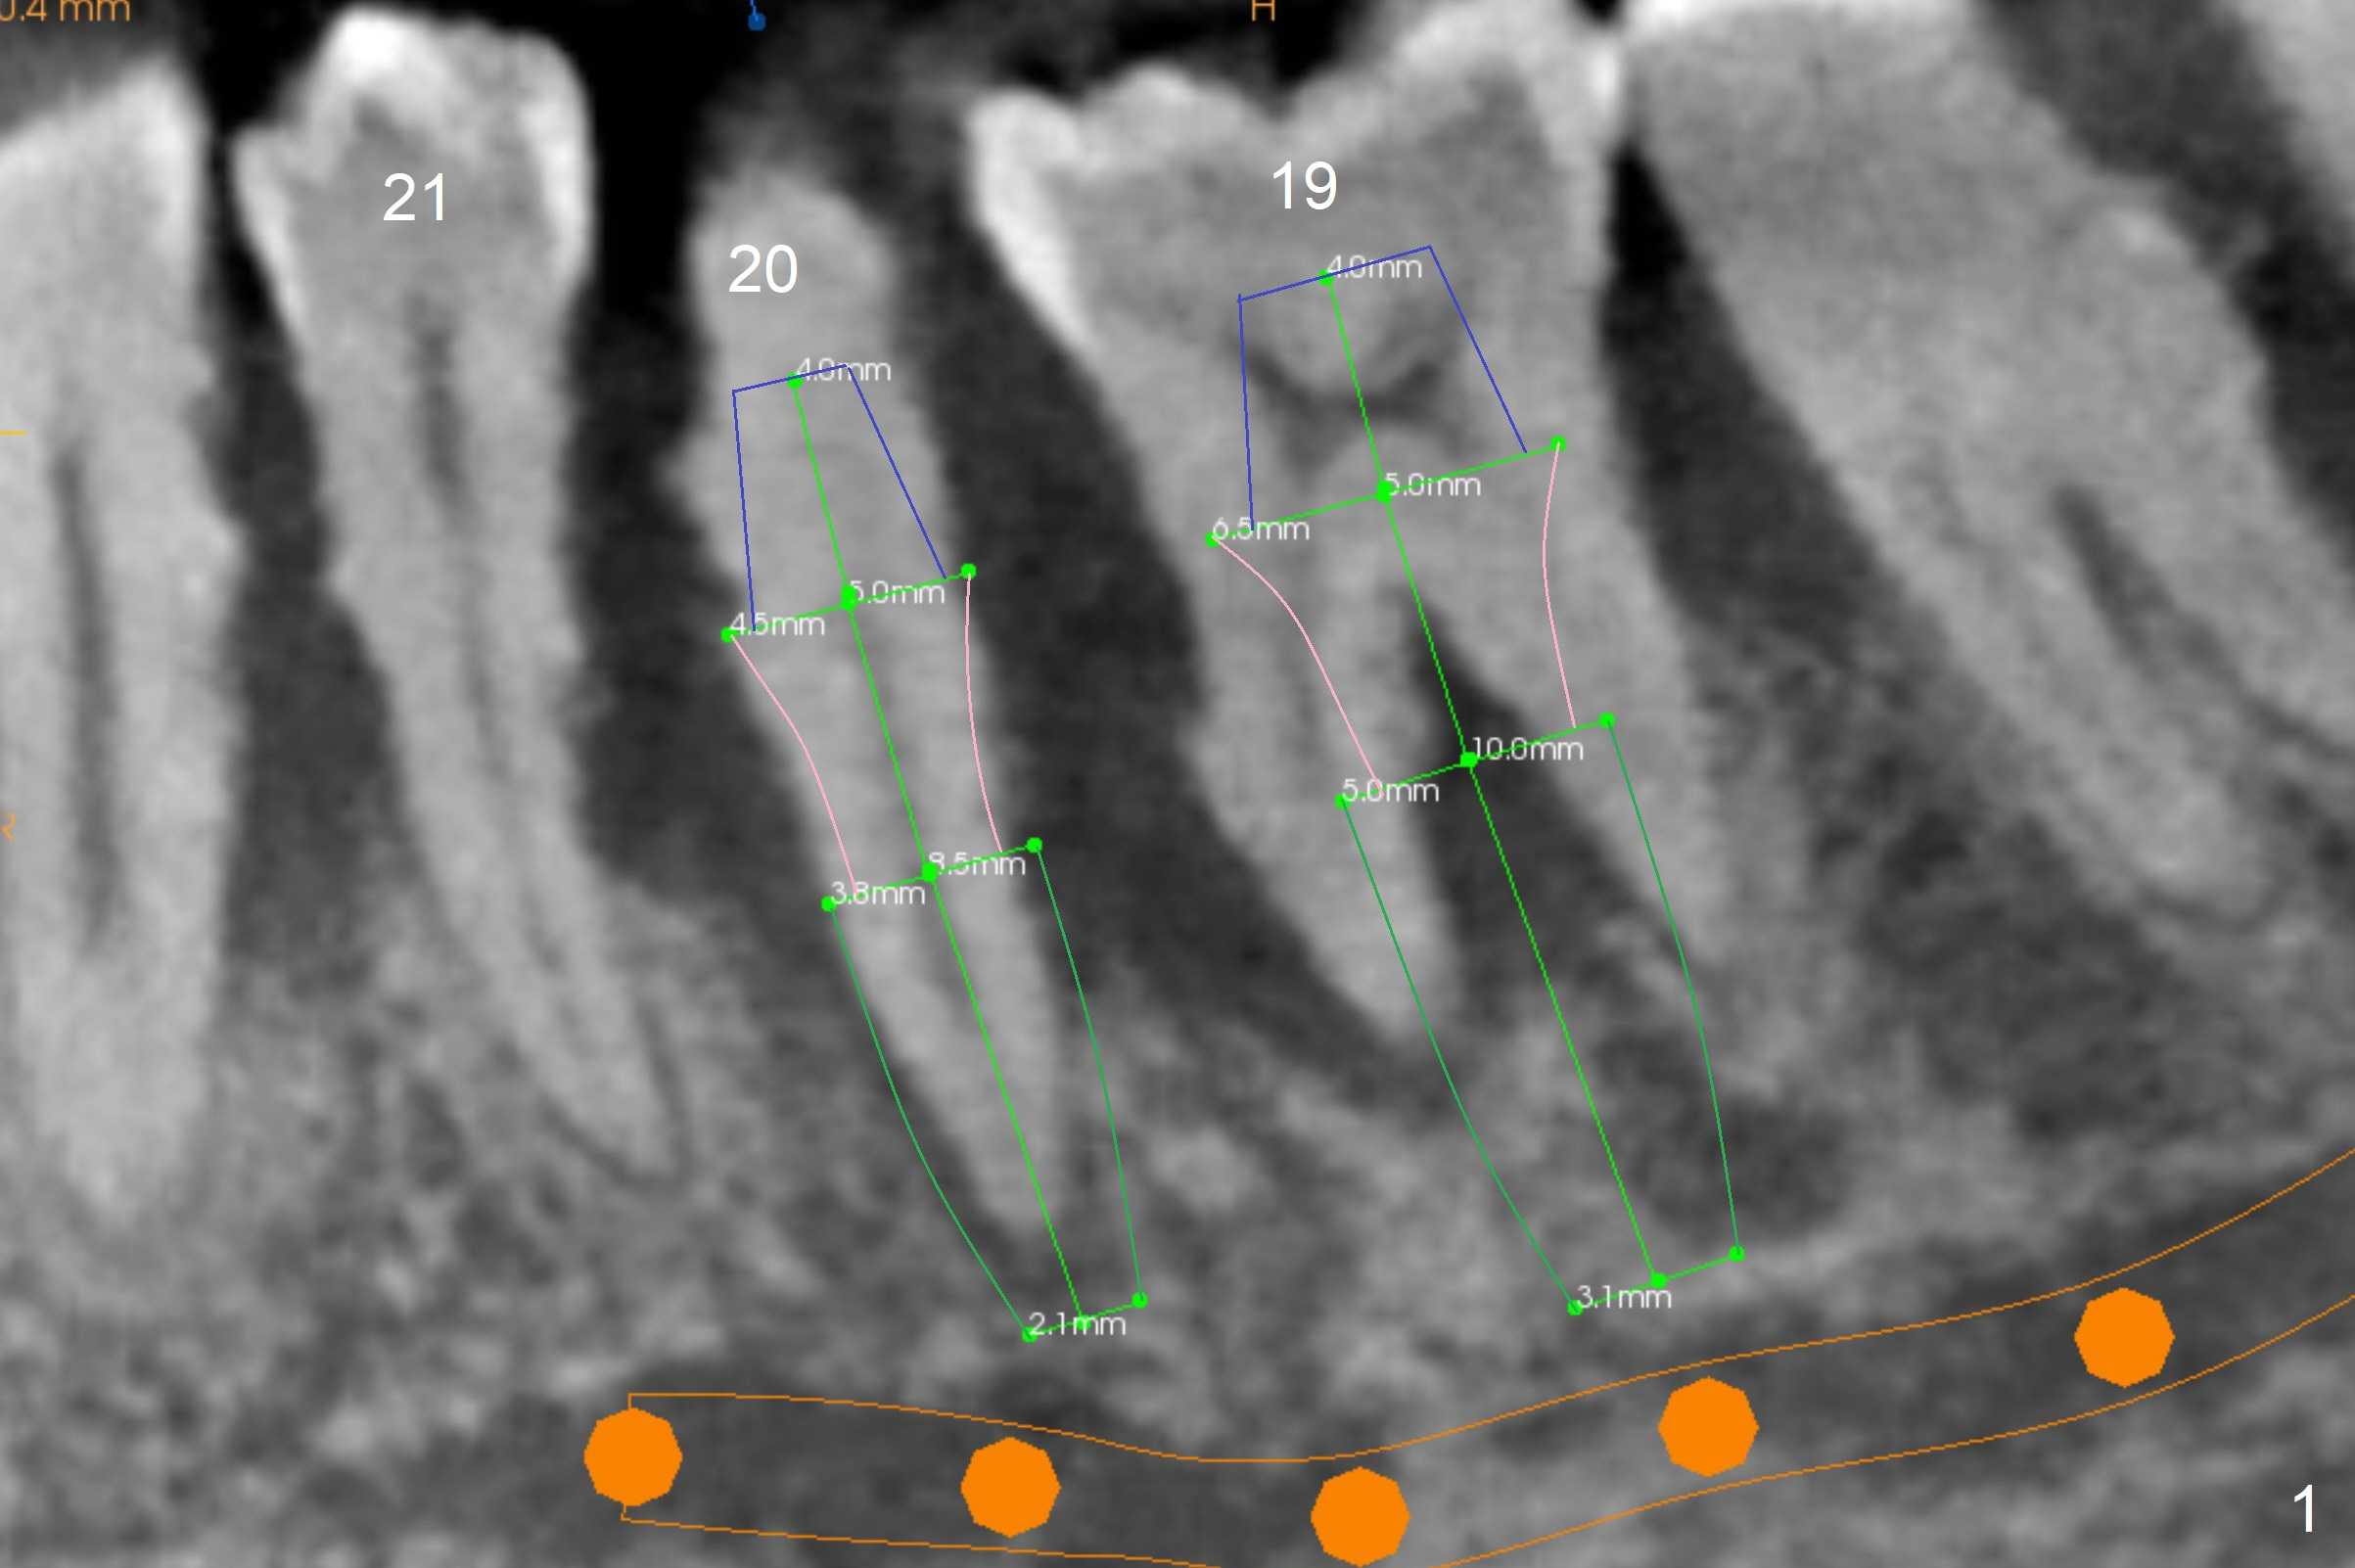

A 36-year-old man develops periodontal abscess at #19 and 20 after scaling & root planing. Since the site of #20 is close to the Mental Nerve, 3.8 mm tap or dummy implant will be used to form osteotomy instead of drills (Fig.1,3). While an implant will be placed in the middle of the socket #20, an implant will be placed as buccal as possible at #19 (Fig.4). If primary stability at #20 is poor, extract the tooth #21 and place a 3.8x10 mm lingually (Fig.2). PRF membrane will be placed prior to bone graft after implant placement (Fig.3 yellow).